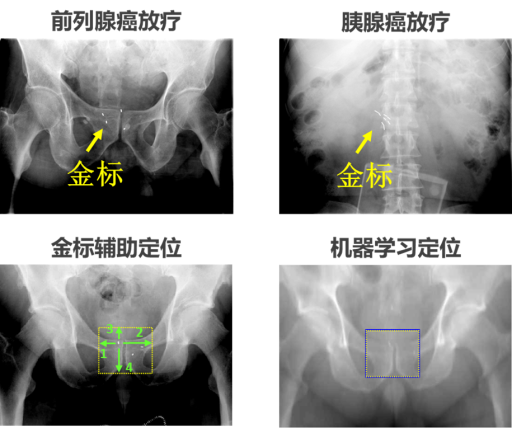

图2. 图像引导放疗

图3. 医学物理人工智能